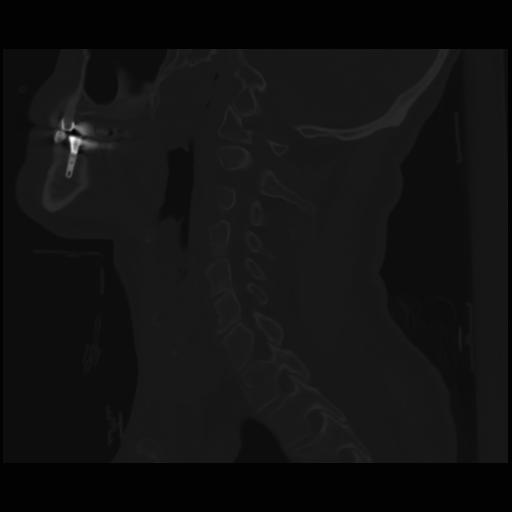

14 P.BLANDAS,,Sagittal,2.000,P.BLANDAS,Sagittal,